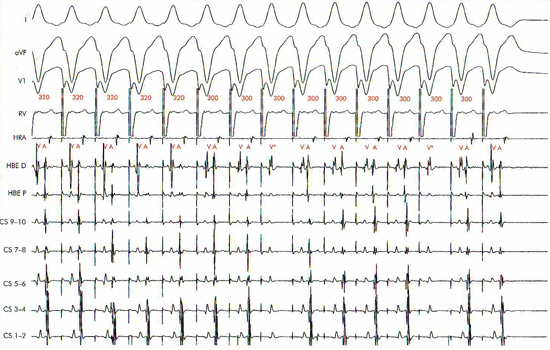

Hình 13: Kích thích thất sớm dần với S1S1: 300 ms gây phân ly thất-nhĩ